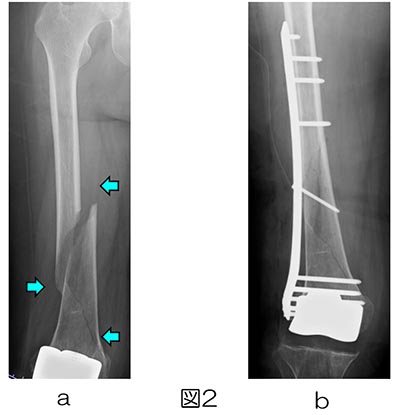

裁断した状態で発送します。\r\r内容紹介\r関節外科医・外傷医ともによく遭遇するインプラント周囲骨折。\rこの分野で初の「教科書」となる本書では上肢から下肢まで骨接合術後・人工関節術後の骨折について幅広く解説しました。\r基礎知識から部位別の治療法、さらには33のケースプレゼンテーションによる具体的な手術手技の内容が盛りだくさん!\r図写真で分かりやすく学ぶことができます。\r付録には良く使うインプラントの一覧と診断・治療に役立つQ&A付き。\rますます増加していく「インプラント周囲骨折」を「極める」ための実践書です。\r\r#整形外科\r#外傷\r#骨折\r#救急\r#手術\r#人工関節\r#サージカルテクニック